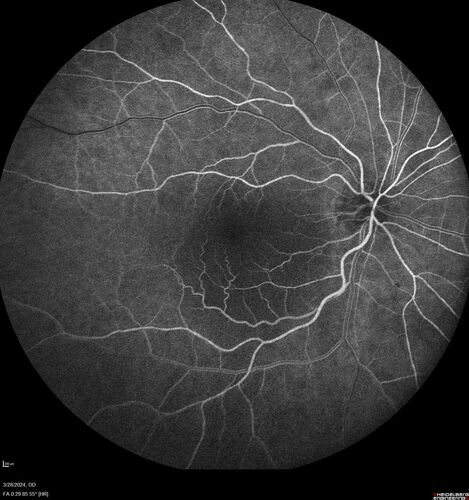

Serous Macular Detachment from Small Choroidal Melanoma

72 year old female misdiagnosed as CSR who had small choroidal melanoms.